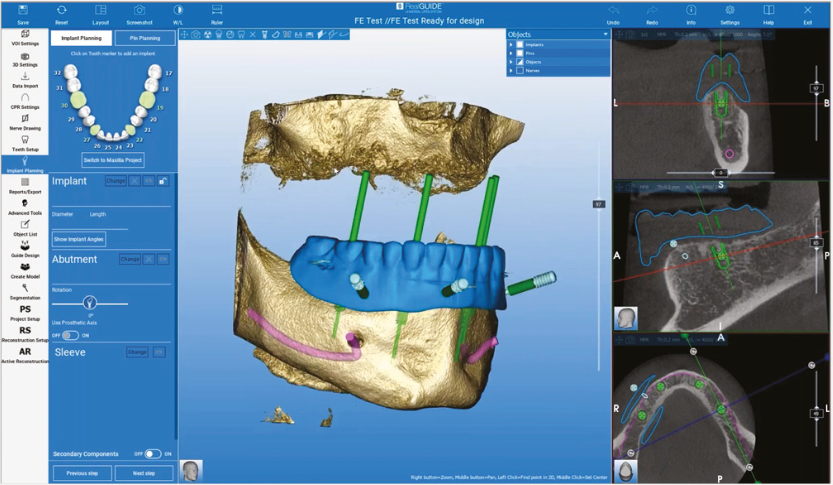

RealGUIDE

Software de imágenes 3D

‧ Amplia biblioteca de implantes

‧ Poderosas herramientas de Inteligencia Artificial (IA)

‧ Infraestructura basada en la nube para la gestión de licencias y bibliotecas

‧ Compatible con Mac, PC o dispositivos móviles iOS

‧ Plataforma integral de comunicación y de uso compartido de archivos

‧ Arquitectura abierta para máxima flexibilidad